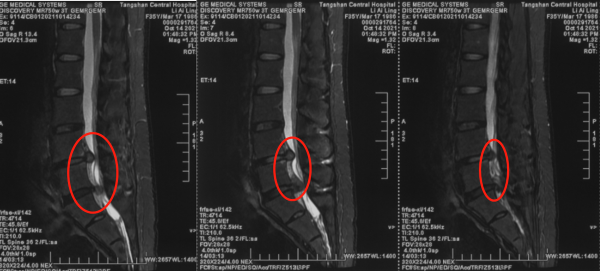

王作偉主任接診後,瞭解了小劉的情況,再根據各項影像學檢查以及詳細查體後,確診她為腰椎間盤突出症(腰4/5、腰5骶1)。王作偉主任表示:從患者的影像學片子上看,可以非常明顯地看到腰4/5、腰5骶1兩個節段的突出,而且已經嚴重的擠壓到後方椎管裡的神經,需要考慮儘快手術減壓。根據患者的病情,又考慮到患者今後還要進行長期訓練以及治療後恢復問題,建議她進行椎間孔鏡手術微創治療。

術前影像學資料: